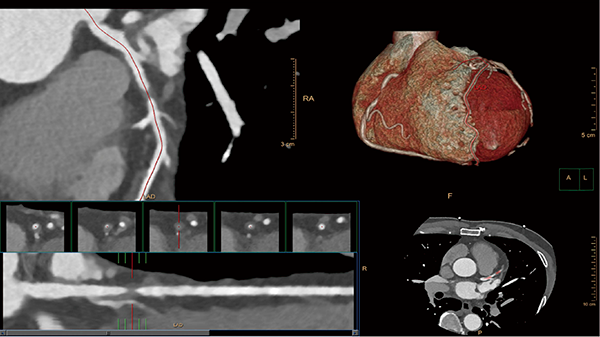

CT用の統合型心臓解析ソフトウェア“Comprehensive Cardiac Analysis(CCA)”は,心臓CTでメインとなるcoronary解析に加え,複数フェーズからの心機能解析まで統合的に解析が行えるように設計されている。最も特徴的なのが,自動セグメンテーション機能によりcoronaryだけではなく左右の心室,心房,心筋まで心臓全体の解剖をセグメンテーションを行う。coronary解析は,ルーチンで行う狭窄率の計測だけではなく,plaque assessmentを追加することで,狭窄部のプラークをボリュームで認識し,ヒストグラムから石灰化やプラークなどの性状を見ることも可能である(図5)。

心機能解析は,従来のシンプソン法と自動セグメンテーションのボリュームを使用するセグメンテーション法が選択できるようになっている。この方法を使用した場合,自動的に心室,心房心筋,大動脈が独立したボリュームとして認識されているため,すぐに左室駆出率(EF)などの値を知ることができる。このように,自動セグメンテーションにより得られた情報を使用することで,少ない手順でcoronaryや心機能の診断を行うことが可能である。

図5 ISPのComprehensive Cardiac Analysisでのcoronary解析